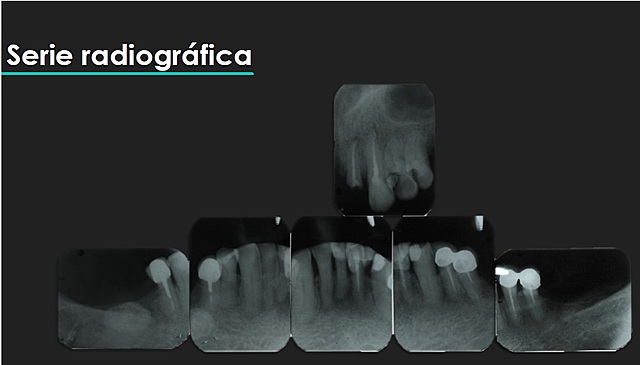

• Serie radiográfica

Serie radiográfica

Al paciente se le realizó una serie radiográfica.

en la serie radiográfica se encuentra una anomalía osea (tours mandibular unilateral)